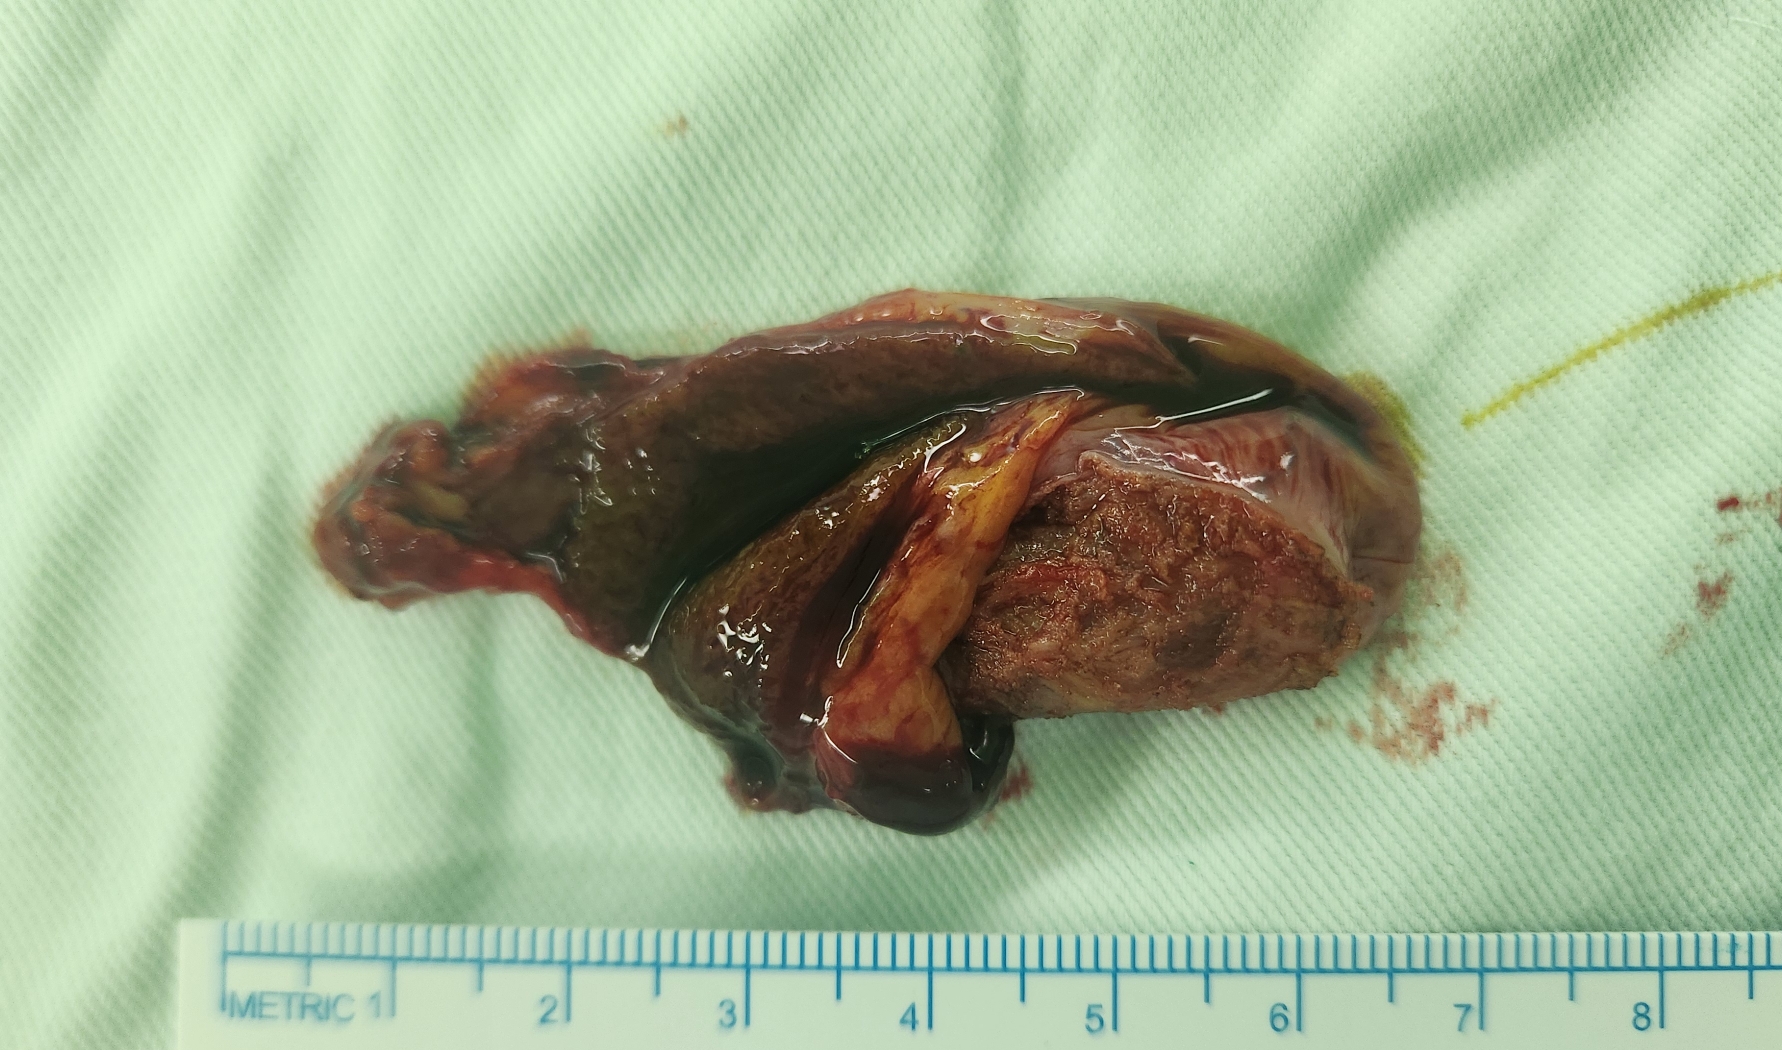

세명기독벙원에서 검진 초음파 시행후 담낭선근증으로 수술 위해 제 외래로 오셨던 분입니다.

방금 단일공 복강경 담낭절제술을 시행했습니다.

수술은 20분 걸렸습니다.